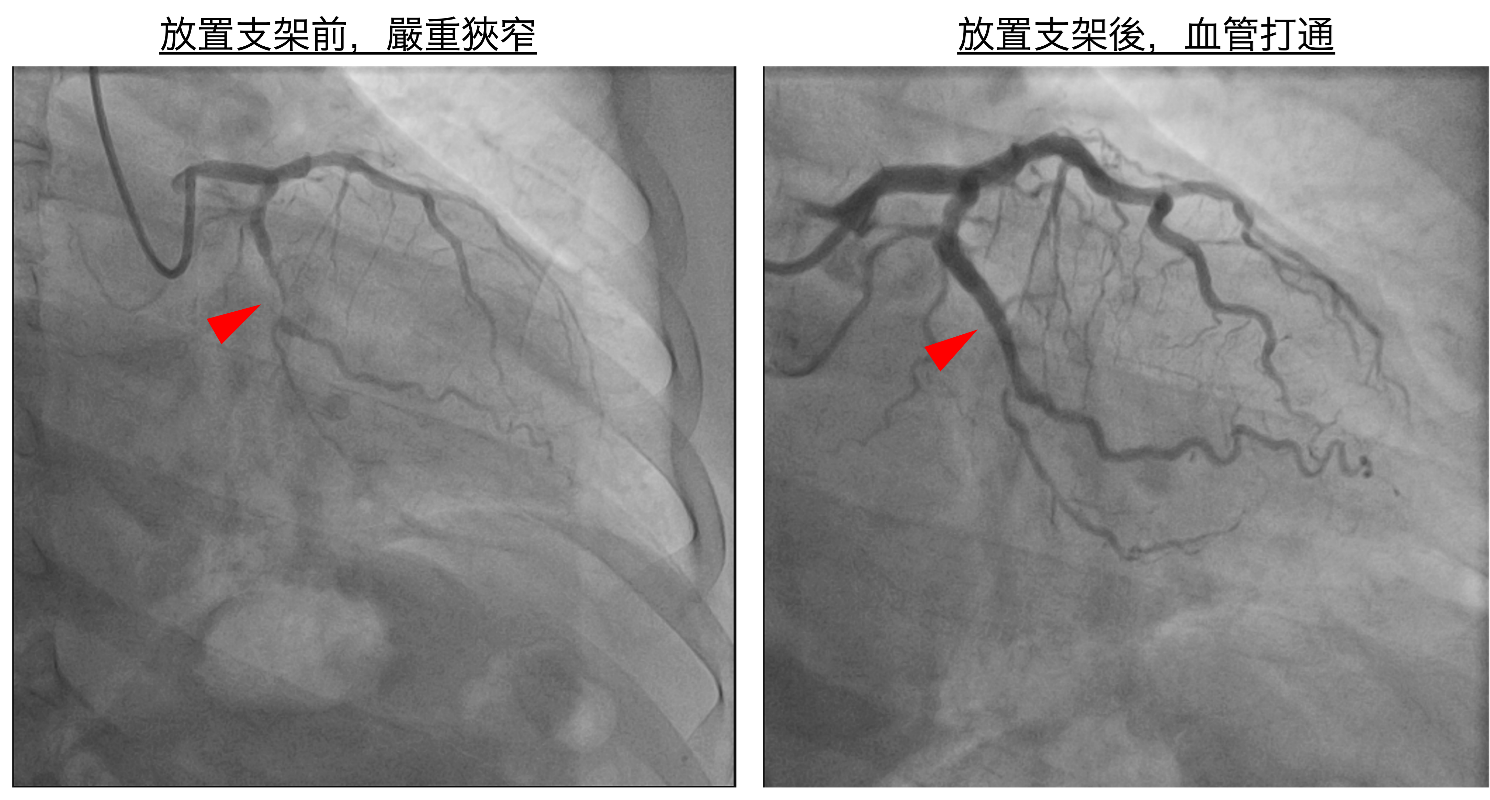

圖一、放置支架前,患者血管嚴重狹窄(左),術後血管打通(右)。

該患者雖規律服藥與追蹤,但多年來始終無法有效控制血壓,因此輾轉來到市立醫院尋求治療。經心血管中心安排精密檢查後,由鍾偉信、簡思齊、陳琦棟醫師施以立體定位腎動脈交感神經消融術改善頑固型高血壓,同時針對冠狀動脈病灶植入鎂合金可吸收支架。手術歷時約兩小時,過程順利。隔日患者即可下床活動,且在未服用降壓藥物的情況下,血壓已降至125~135/80~85 mmHg。另外,患者LDL高達200 mg/dL,屬心血管極高危險群,加上近期剛治療腎結石,醫師建議搭配目前最新一代降脂針劑治療,副作用低。患者對於能一次整合處理高血壓、動脈狹窄及血脂問題,深感安心,因為鍾醫師能聽懂他對副作用的擔憂,並表示終於找到「能改善病根」的治療方式。

年輕患者首選:可吸收支架保留血管彈性

年輕患者若以傳統金屬支架治療,血管會因永久性金屬結構而失去自然舒縮能力。第三代鎂合金可吸收支架初期能穩定撐開血管,一年內約99%會被身體吸收,不會殘留異物或造成長期發炎,對保留未來血管健康十分有利。但前提須血管無嚴重鈣化、長度短、無大分支之情形,才能評估使用。